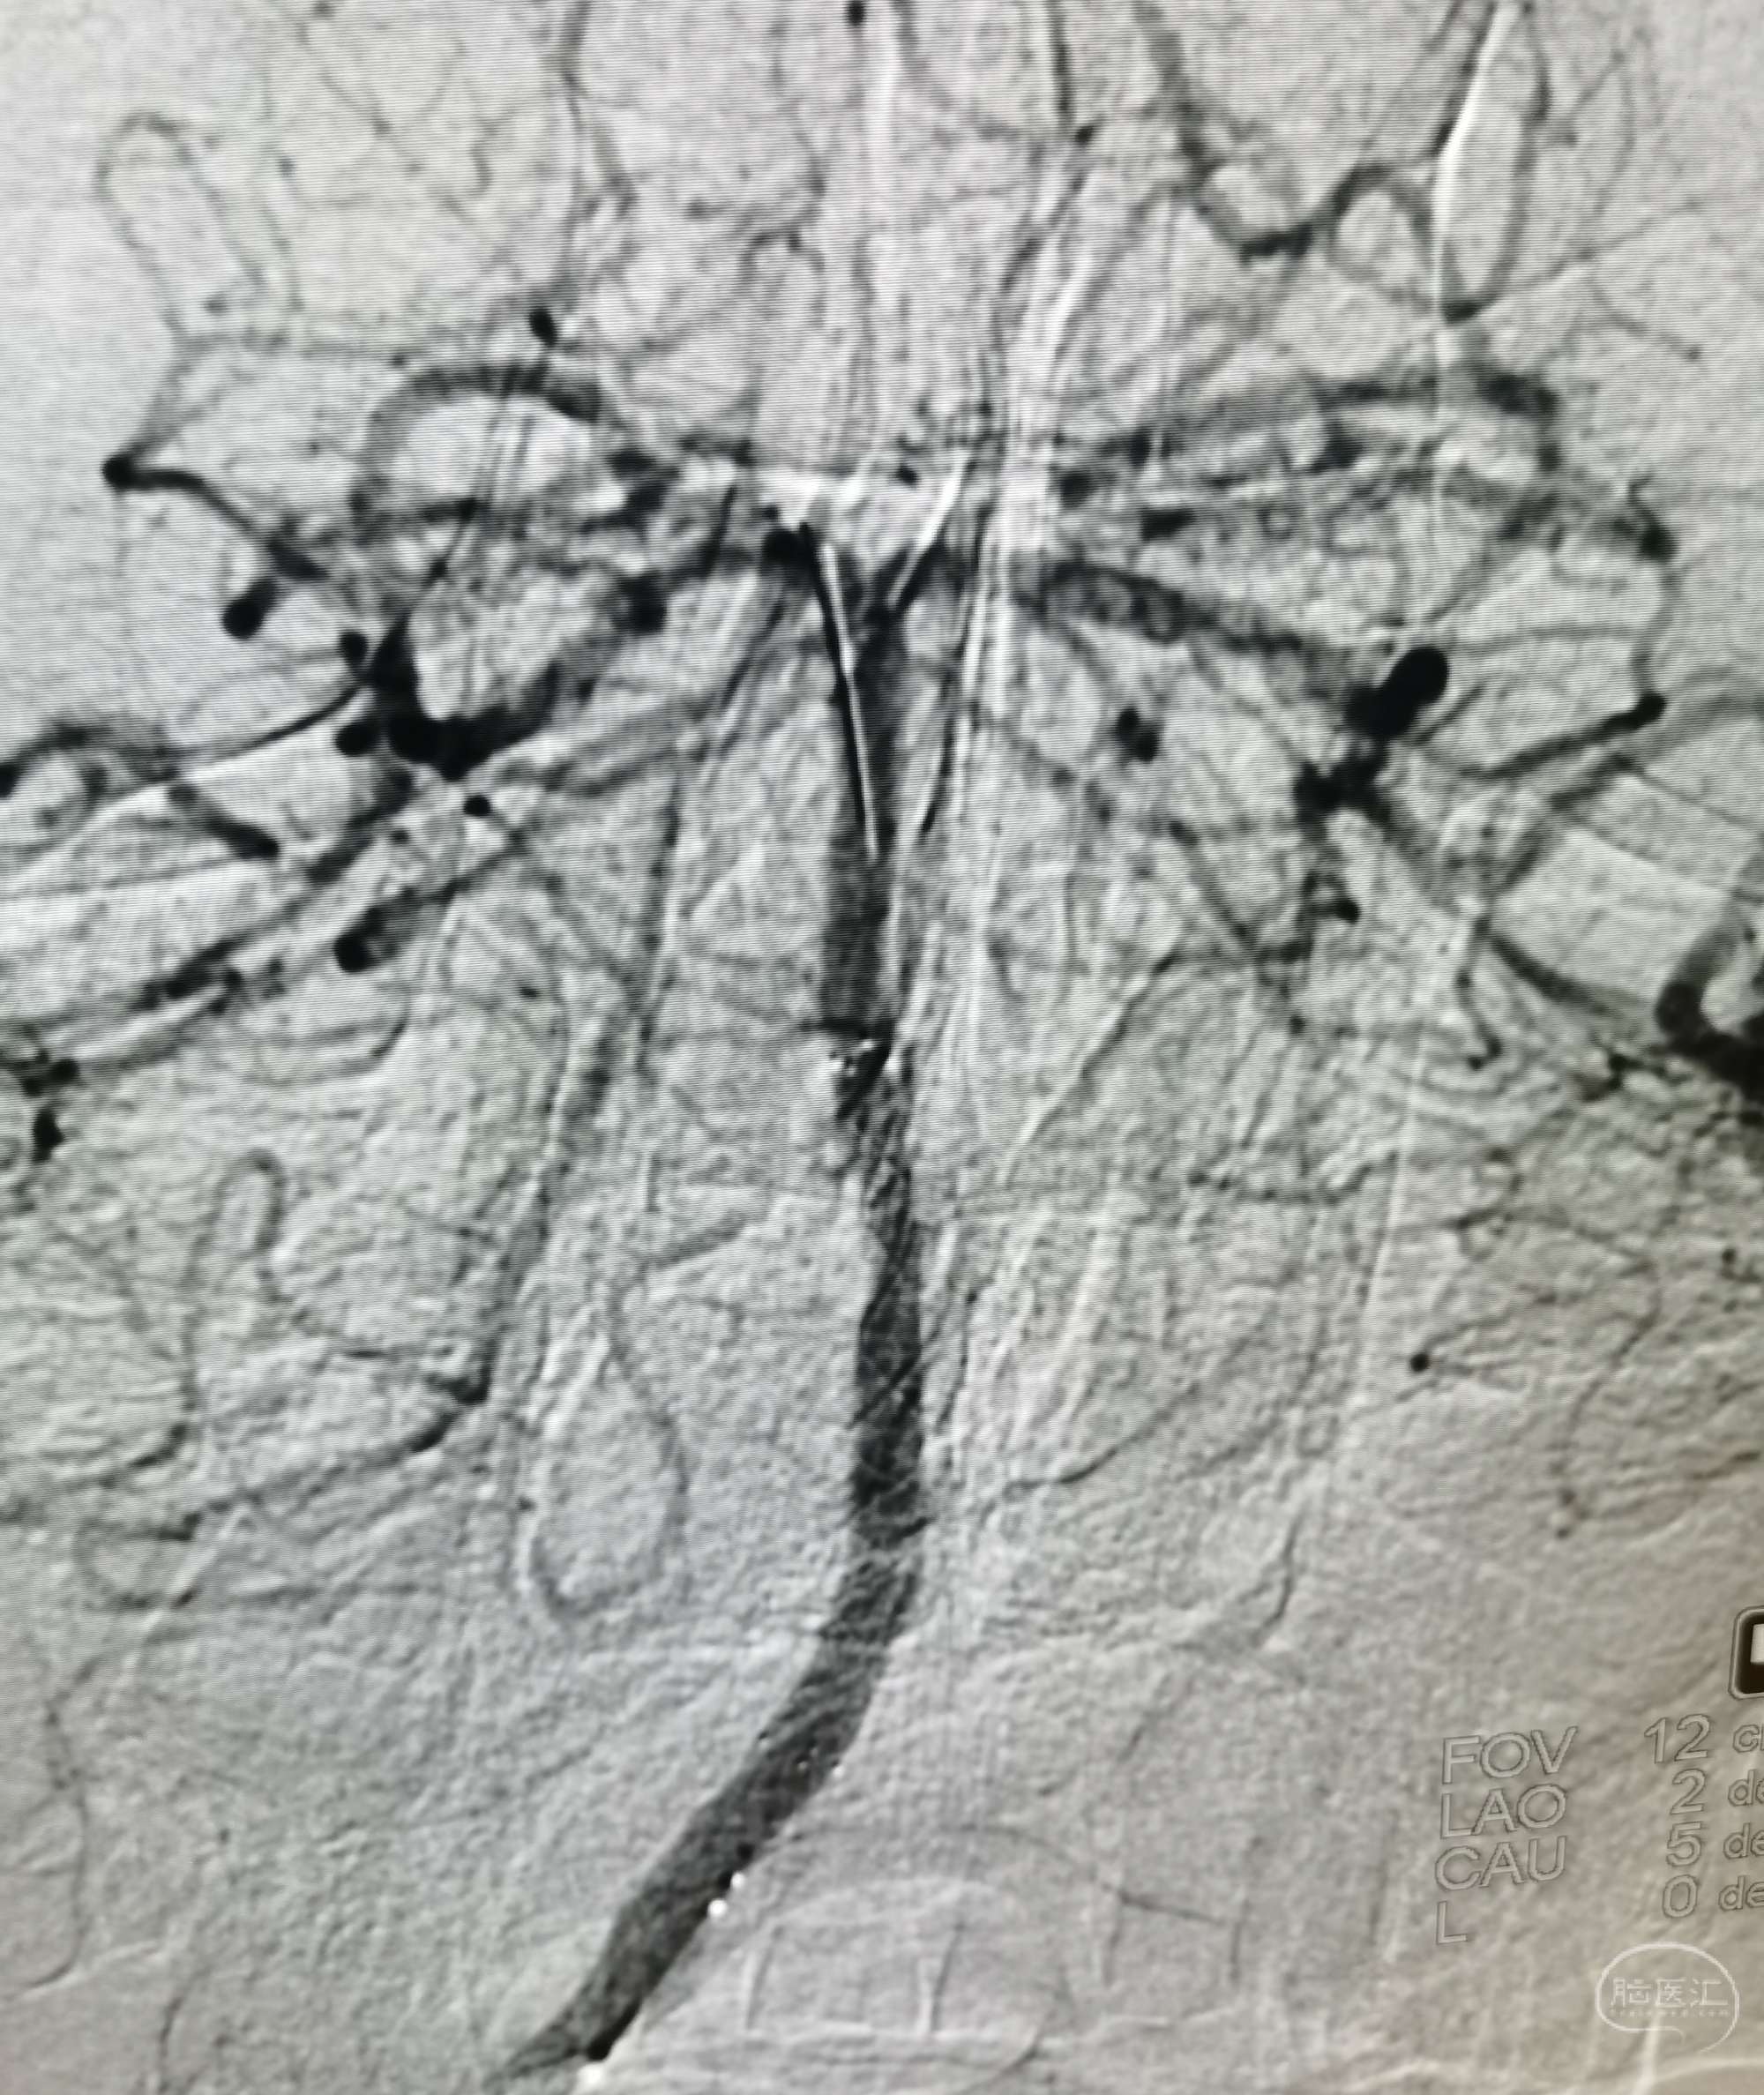

病例4 中年女性,因脑梗塞入院。诊断:左侧颈动脉闭塞。

DSA:左侧颈内动脉闭塞。

颞浅动脉未向颅内代偿。

行颞浅动脉-M4端侧吻合。

吻合14针。

荧光造影示:吻合桥动脉通畅。